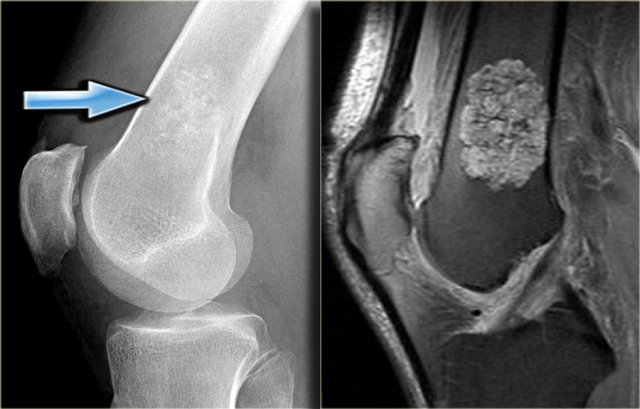

Here a lesion located in the epi- and metaphysis of the proximal humerus.

The lesion is predominantly calcified.

Coronal T1W image shows lobulated margins and peripheral low SI due to the calcifications.

Click here for more examples of chondroblastoma.

Plain radiograph and coronal T1-weighted contrast-enhanced fat-suppressed MR image of a mixed lytic and sclerotic lesion of the distal femoral diaphysis.

Notice the homogeneous thickening of the cortical bone.

There are no calcifications.

The MR image shows that the lesion has lobulated contours and nodular enhancement.

The homogeneous enhancement in the upper part with edema and cortical thickening are not typical for a low-grade chondrosarcoma.

A high grade chondrosarcoma must be considered in the differential diagnosis.

Biopsy revealed dedifferentiated chondrosarcoma.